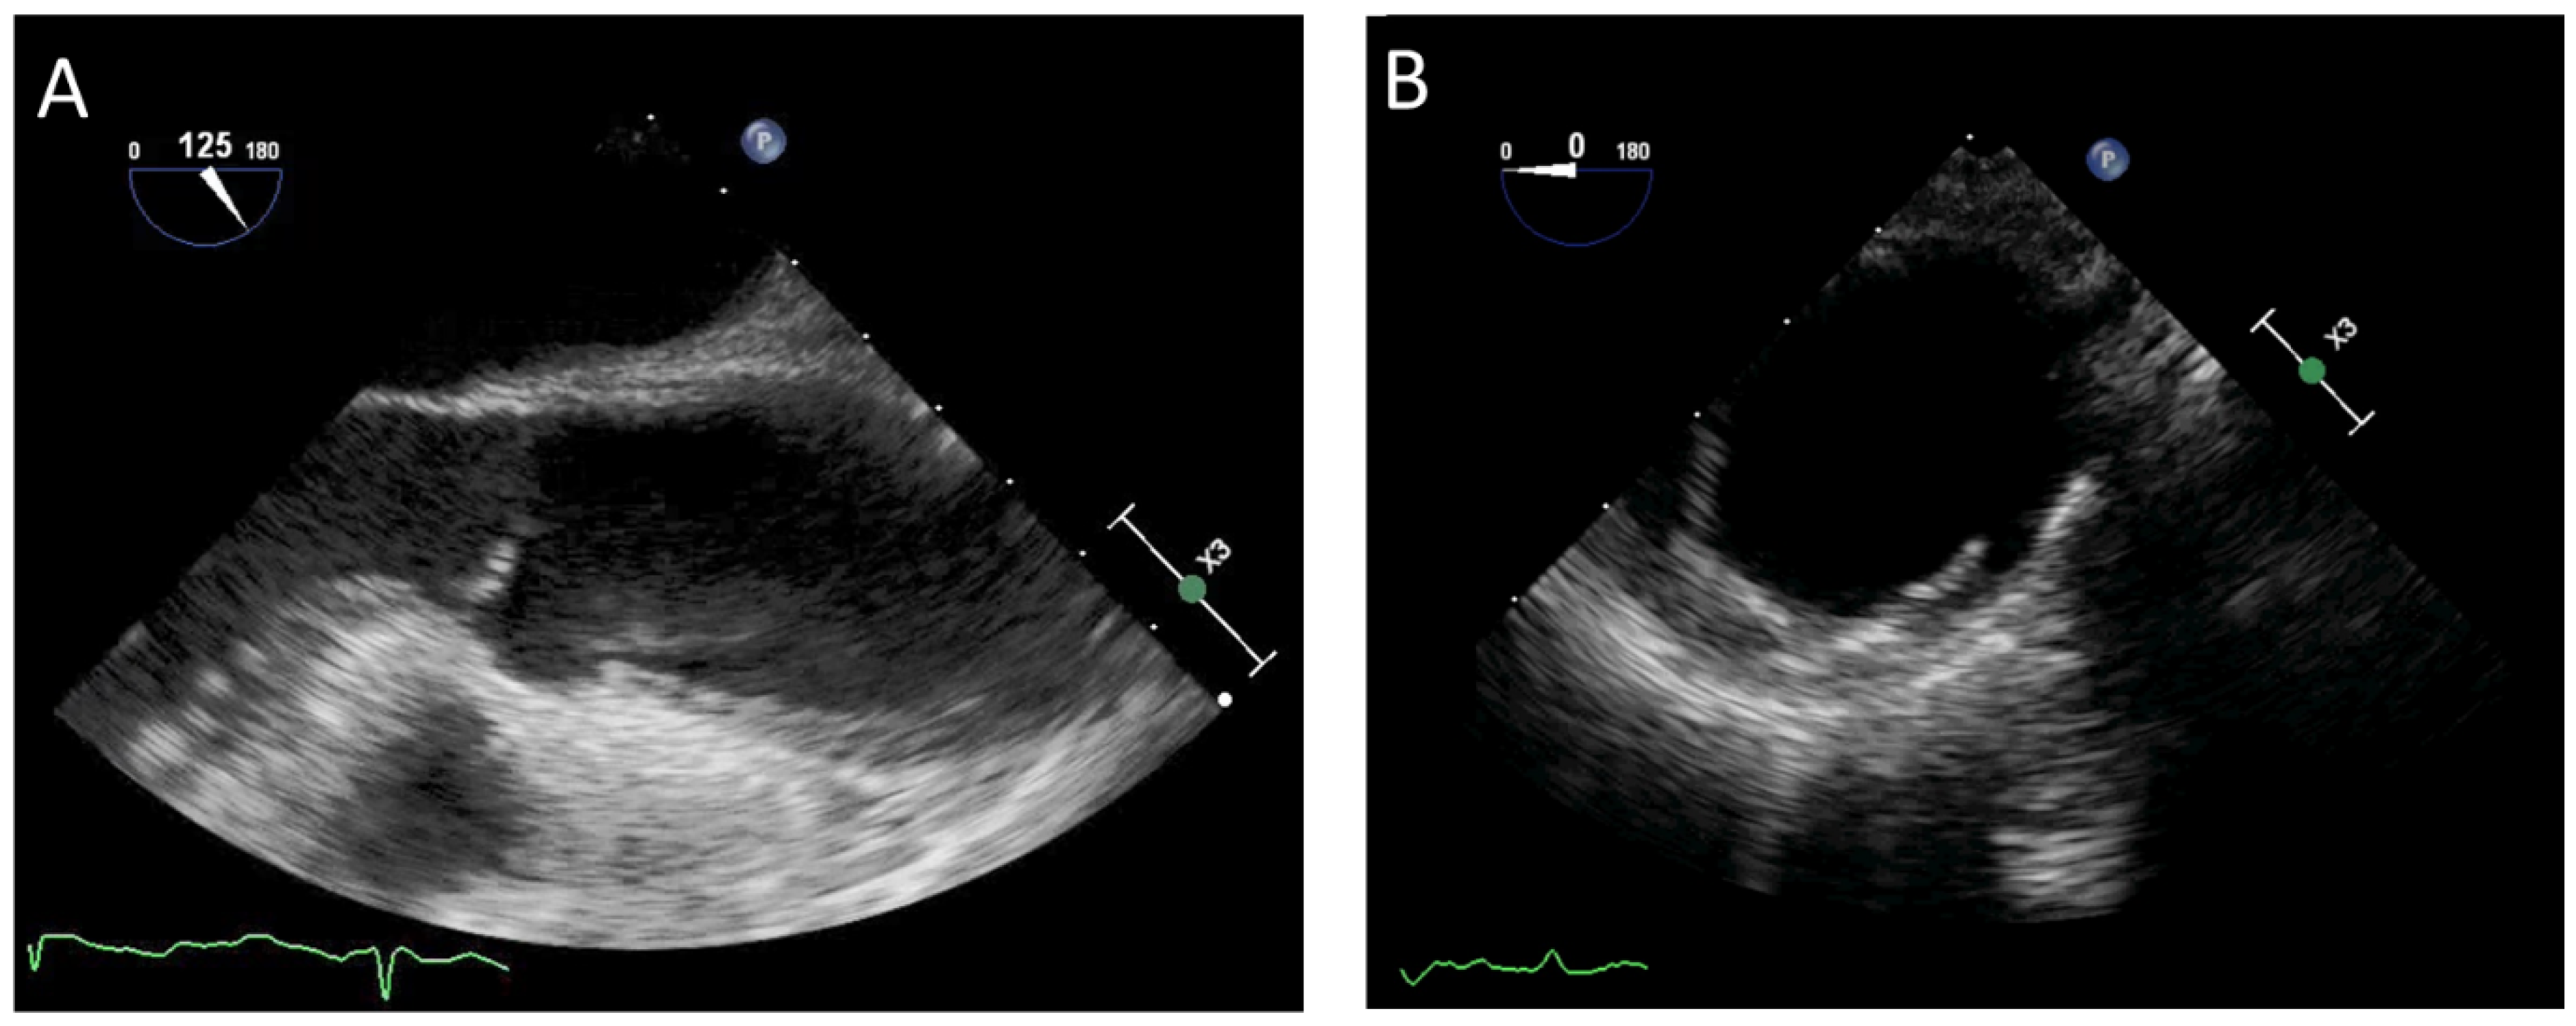

Figure 2.

Transesophageal echocardiography assessment in two different patients with acute aortic syndrome: (A) intramural hematoma and (B) penetrating aortic ulcer.